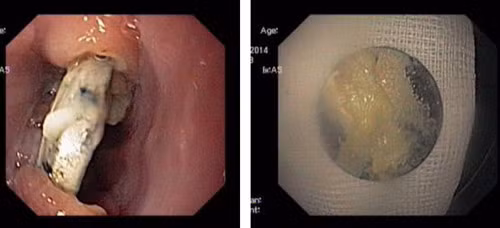

| Cục pin trong thực quản cháu bé và khi được lấy ra. |

Theo các bác sĩ khoa Nội – Tiêu Hoá, Bệnh viện Nhi T.Ư, cho biết, sau khi thăm khám và hụp X-quang phổi, họ phát hiện dị vật hình tròn cản quang nằm ở đốt sống ngực của bé. Kết quả nội soi cho thấy, tại đoạn thực quản trên có hình ảnh dị vật tròn găm vào hai thành thực quản, làm cho thực quản của bé bị loét sâu, rớm máu.

Khi dị vật được gắp ra, các bác sĩ và người nhà em bé đều bất ngờ vì đó là một quả pin điện tử tròn có đường kính 1,5 cm đã hoen gỉ xung quanh.